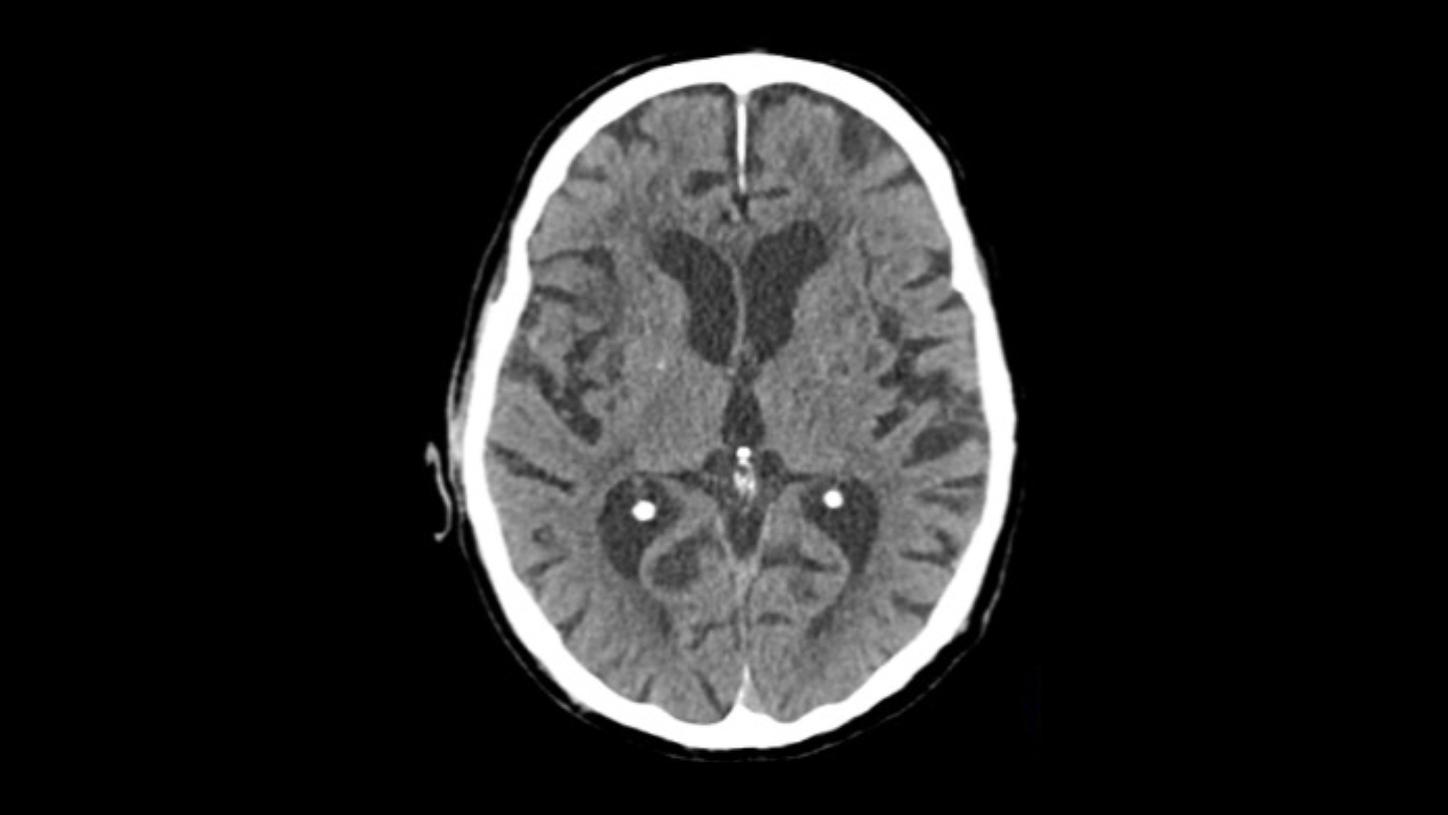

Native head scan

Assist with or support differential diagnosis of acute stroke with excellent gray-white matter differentiation and contrast enhancement